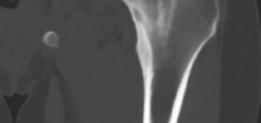

High-resolution, thin-slice computed tomography (CT) with multiplanar reconstruction is the gold standard for defining the osseous anatomy. The CT scan accurately delineates the nidus as a well-circumscribed, radiolucent focus, often containing a central fleck of mineralization, surrounded by varying degrees of sclerosis. The surgeon must meticulously map the location of the nidus relative to reliable arthroscopic landmarks, such as the medial synovial fold, the zona orbicularis, and the articular margin of the femoral head.

Locating the nidus is the most challenging aspect of the procedure. The overlying cortex may appear entirely normal, or it may exhibit subtle neovascularization, a localized hyperemic blush, or a slight cortical prominence.

The surgeon uses a combination of preoperative CT mapping, direct arthroscopic visualization, and intraoperative fluoroscopy to pinpoint the lesion. A spinal needle or a Kirschner wire is introduced percutaneously and advanced to the suspected location on the femoral neck. AP and lateral fluoroscopic views are obtained to confirm the trajectory and depth relative to the radiolucent nidus.

Once the location is confirmed, a high-speed arthroscopic burr is used to carefully unroof the overlying cortex. As the cortex is breached, the nidus typically appears as a distinct, hyperemic, cherry-red, granular tissue mass that contrasts sharply with the surrounding white, sclerotic bone.